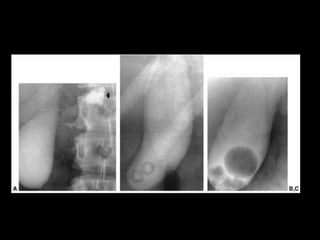

• Rx:

– 10 – 15% das colelitiases, estão calcificadas e

identificáveis no RX

– Pode ser visto também a vesícula em “porcelana.”

– Gás pode ser visto dentro das pedra: Sinal de

Mercedes-Benz

– Colecistografia oral: Ingesta de composto iodado.

Atualmente susbstituído pelo US

Técnicas de Imagem •Rx: – 10 – 15% das colelitiases, estão calcificadas e identificáveis no RX – Pode ser visto também a vesícula em “porcelana.” – Gás pode ser visto dentro das pedra: Sinal de Mercedes-Benz – Colecistografia oral: Ingesta de composto iodado. Atualmente susbstituído pelo US